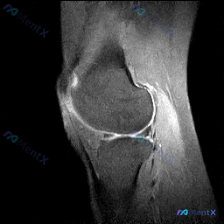

给大家分享一个很有启发的膝关节MRI读片病例,临床关注点是半月板异常,读完片发现其实核心问题不在这儿,整理一下完整分析思路。 病例影像基本信息 这是一份膝关节矢状位T2加权MRI(压脂序列),我们先整理所有客观发现: 1. 关节内结构:半月板形态完整,呈典型低信号三角表现,未见贯穿性高信号,边缘光滑...

看到一份很有启发的膝关节MRI病例,初始提示是「半月板异常」,但读片后的发现和一开始的方向完全不一样,整理一下完整分析思路跟大家分享。 一、病例影像基础信息 这是膝关节MRI矢状位T2加权图像,我们先整理所有客观发现: 1. 骨骼关节:股骨远端、胫骨近端、髌骨骨皮质完整,无明显骨折或骨质破坏,髌骨与...

病例读片分享:临床怀疑半月板异常,MRI却只看到髌周病变 基本影像信息 提供的影像为膝盖MRI-T2序列矢状位,切面位于膝关节前部髌股关节区域,图像存在一定截断伪影,未显示后交叉韧带及大部分后侧软组织结构。 影像核心发现 整理一下客观观察到的异常: 1. 髌前皮下软组织水肿:髌骨前方及皮下组织层可见...

看到这份有意思的病例,主诉是提示半月板异常的膝关节MRI,整理了完整的读片思路和分析,分享给大家。 一、影像基础信息 这是一幅膝关节MRI T2加权矢状位图像,我们先确认基础信息: - 成像序列符合T2WI特征:液体高信号、软骨中等信号、脂肪低信号、骨皮质及韧带低信号 - 切面展示膝关节前部结构:髌...